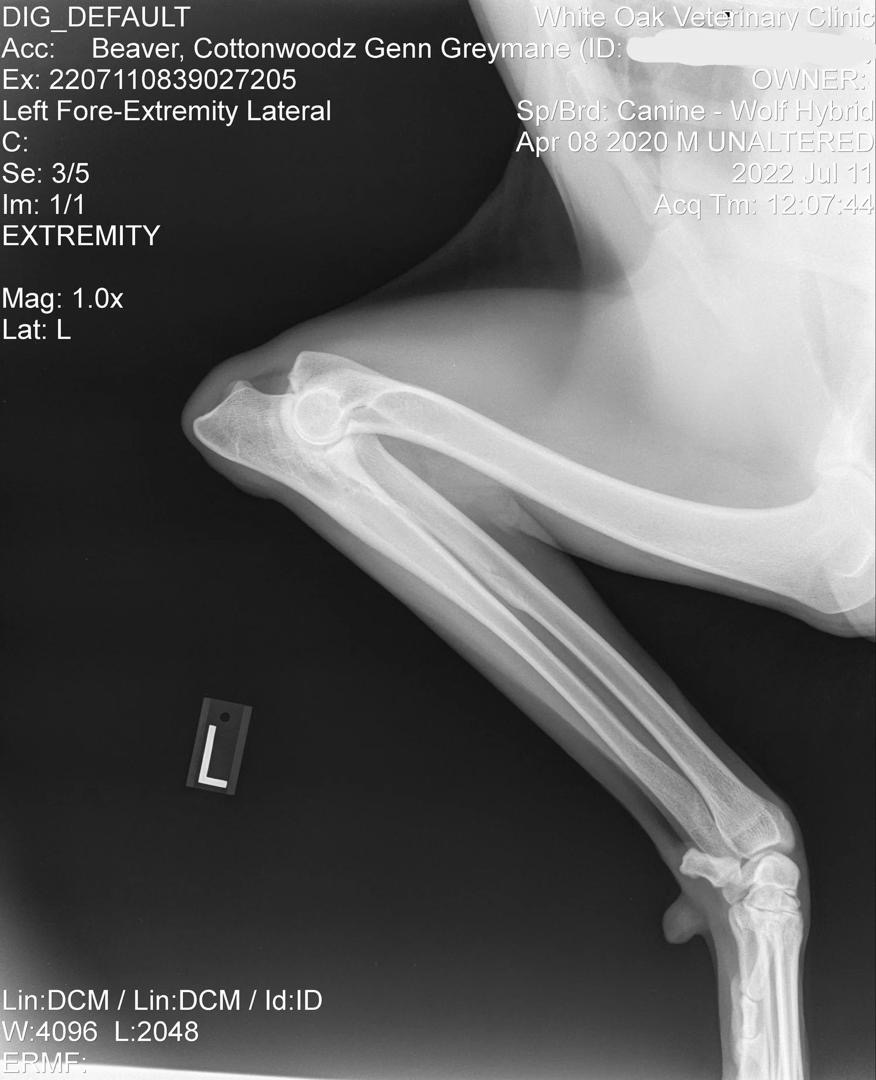

Genn Official Left Elbow X-Ray

Official Left Elbow X-Ray

OFA Elbow Evaluation: Normal